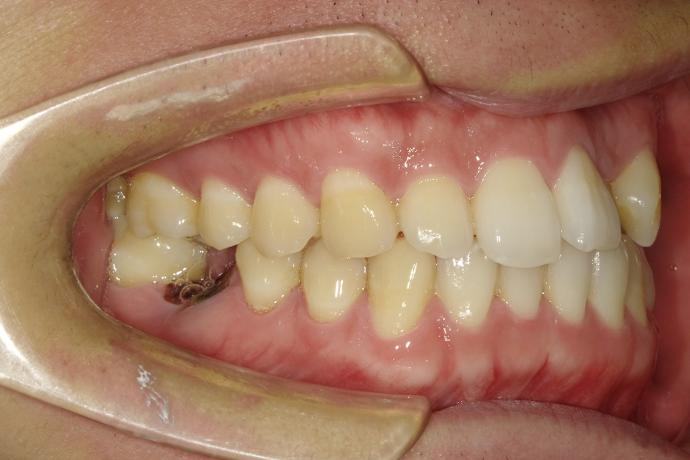

術後

如今年輕帥氣的小老闆,不再受缺牙之苦,可以開心的享受美食了